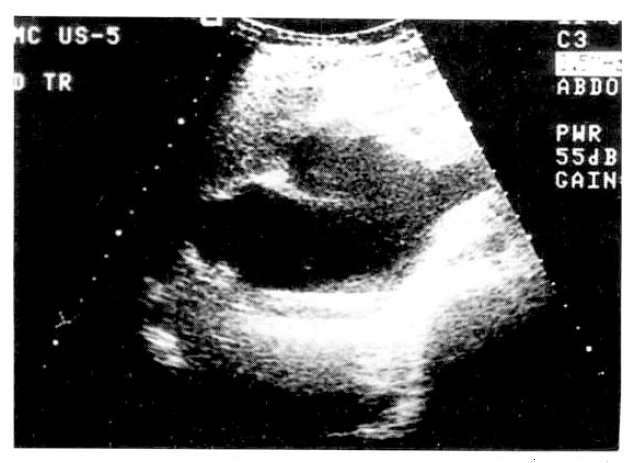

A 29-year-old nulliparous woman at 32nd week gestation began experiencing epigastric burning and back pain associated with nausea and vomiting. She had no significant gynecological, past medical history. She denied any drug ingestion, foreign travel or recent contact with infectious disease and there was no history of fatty food intolerance or long standing indigestion. On examination, the patient was afebrile with normal vital signs. She was not anemic or jaundiced. Abdominal palpation confirmed tenderness in the epigastrium. Fetal movements were felt and the uterus was of an appropriate size for gestational age. The full blood count showed leukocytosis of 12000/mm3 and serum amylase 174U/L (normal 30–110U/L) and lipase 1297U/L (normal 23–300 U/L) were elevated. Laboratory values revealed total bilirubin of 1.2mg/dl, direct bilirubin 0.7mg/dl, alkaline phosphatase 189IU/L, AST 71U/L, ALT 73U/L. The hepatitis screens were negative. All other laboratory values were within normal limits. A diagnosis of acute pancreatitis was made. Ultrasonography of the abdomen identified the gall bladder to be normal and the intrahepatic ducts were not dilated. A large choledochal cyst was noted high in the portahepatis (Fig. 1). The pancreas appeared swollen and echolucent consistent with acute pancreatitis. An ongoing intrauterine pregnancy was confirmed, fetal ultrasonography was consistent with that of a 34th week fetus and showed no evidence of growth retardation. On the 15th hospital day, the patient began experiencing abdominal pain. Because the fetus was known to be mature, it was elected to proceed with cesarean section. With the patient under general endotracheal anesthesia, the infant was delivered without difficulty. On the 27th hospital day, endoscopic retrograde cholangiopancreatogram was performed. The injected contrast material showed a markedly dilated choledocal cyst in the common bile duct (Fig. 2). On the 33rd hospital day, arrangement was made for laparotomy to operate on the choledochal cyst. During the operation, she was found to have a large type I choledochal cyst. Resection of the choledochal cyst was performed and a Roux-en-Y hepatico-jejeunostomy was carried out to provide biliary drainage. The procedure was well tolerated and she made an uncomplicated recovery.

Fig. 2.

The injected contrast material showed a markedly dilated choledochal cyst in the common bile duct.